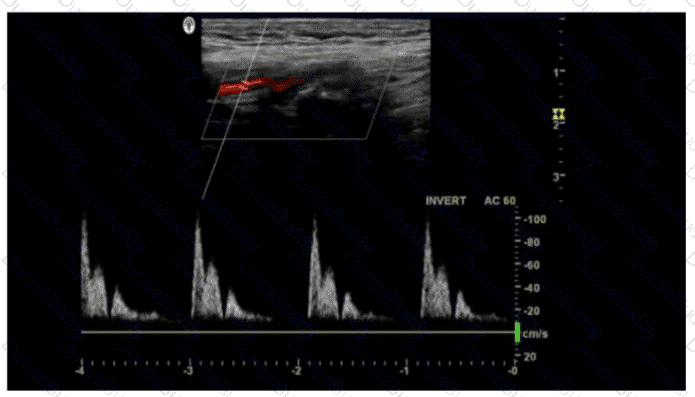

Questions 31

In this image, which artifact is demonstrated?

SPI Question 31

Options:

A.

Mirroring

B.

Aliasing

C.

Range ambiguity

D.

Spectral broadening